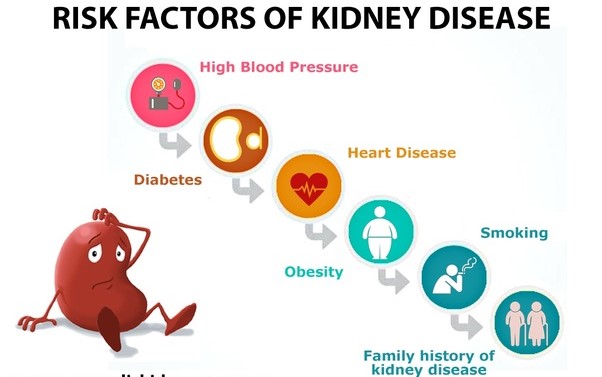

اکثر بیماریهای کلیوی به نفرونها حمله میکنند. این آسیب گاهی باعث میشود که کلیهها دیگر نتوانند مواد زائد را از بدن خارج کنند. از علل بروز بیماریهای کلیه میتوان به مشکلات ژنتیکی، صدمه دیدن یا مصرف دارو اشاره کرد. ابتلا به دیابت، فشار خون بالا یا ابتلا یکی از خویشاوندان نزدیک به بیماری کلیوی احتمال بروز ناراحتی کلیه را افزایش میدهد. بیماری مزمن کلیه و نارسایی کلیه به آهستگی و ظرف چندین سال به نفرونها آسیب میزند. دیگر ناراحتیهای کلیه عبارتاند از:

ناراحتی کلیه معمولاً هر دو کلیه را درگیر میکند. اگر بیماری توانایی کلیه را در دفع و تنظیم آب و مواد شیمیایی مختل کند، مایع اضافی و مواد زائد در بدن جمع میشود و علایم و ورم شدید اورمی (نارسایی کلیه) بروز مییابد. بیماری کلیه انواع و علل متفاوتی دارد که میتوان آنها را به سه دسته ارثی، مادرزادی یا اکتسابی تقسیم کرد.